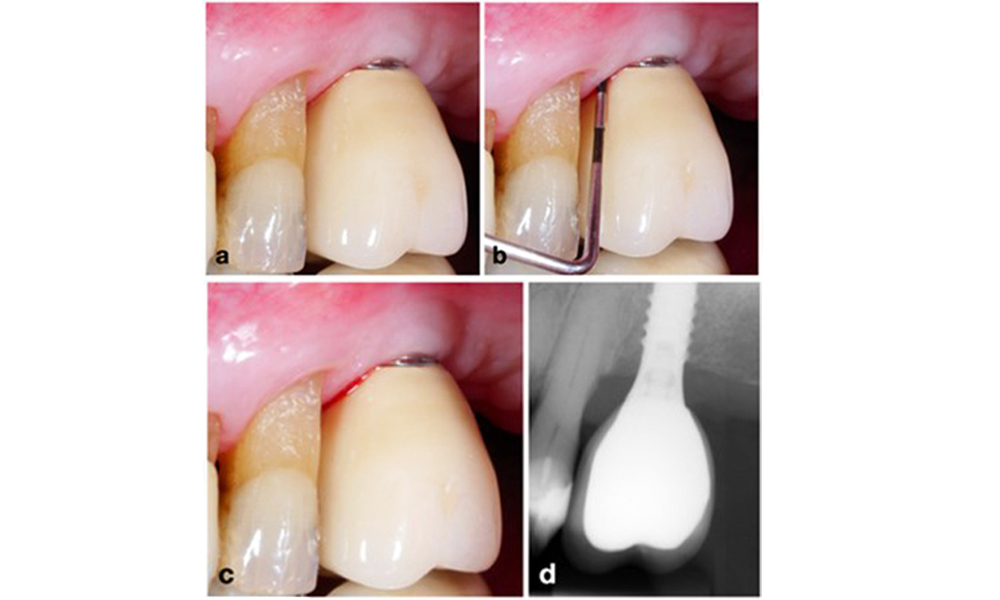

Auf dem World Workshop on the Classification of Periodontal and Peri‐Implant Diseases and Conditions 2017 wurden diagnostische Kriterien für periimplantäre Mukositis und Periimplantitis festgelegt (Renvert et al. 2018). Periimplantäre Mukositis ist definiert als (1) Entzündung um das Implantat (also Rötungen, Schwellungen, Blutfäden oder Blutstropfen innerhalb von 30 Sekunden nach dem Sondieren), jedoch (2) ohne zusätzlichen Knochenverlust nach der Ersteinheilung (Abb. 1).

Periimplantitis ist zu erkennen an (1) Entzündungszeichen, vergleichbar einer Mukositis, (2) einem radiologischen Nachweis von Knochenverlust nach Ersteinheilung und (3) der Zunahme der Sondierungstiefe im Vergleich zu Messungen kurz nach dem Einsetzen der prothetischen Rekonstruktion (Abb. 2). Liegen keine früheren Röntgenaufnahmen vor, weisen ein radiologisches Knochenniveau von ≥ 3 mm zusammen mit Sondierungsblutungen und Sondierungstiefen von ≥ 6 mm auf eine Periimplantitis hin.

Der erwartete Knochenverlust nach Ersteinheilung ist auf die marginale Knochen-Remodellierung zurückzuführen und variiert in Abhängigkeit von Faktoren wie Implantatsystem oder Implantattyp.

Ein Knochenverlust von 1–2 mm gilt beispielsweise bei Implantaten auf Knochenniveau mit Außenverbindung allgemein als „normal“ (Abb. 2d, Implantat an Position 23).